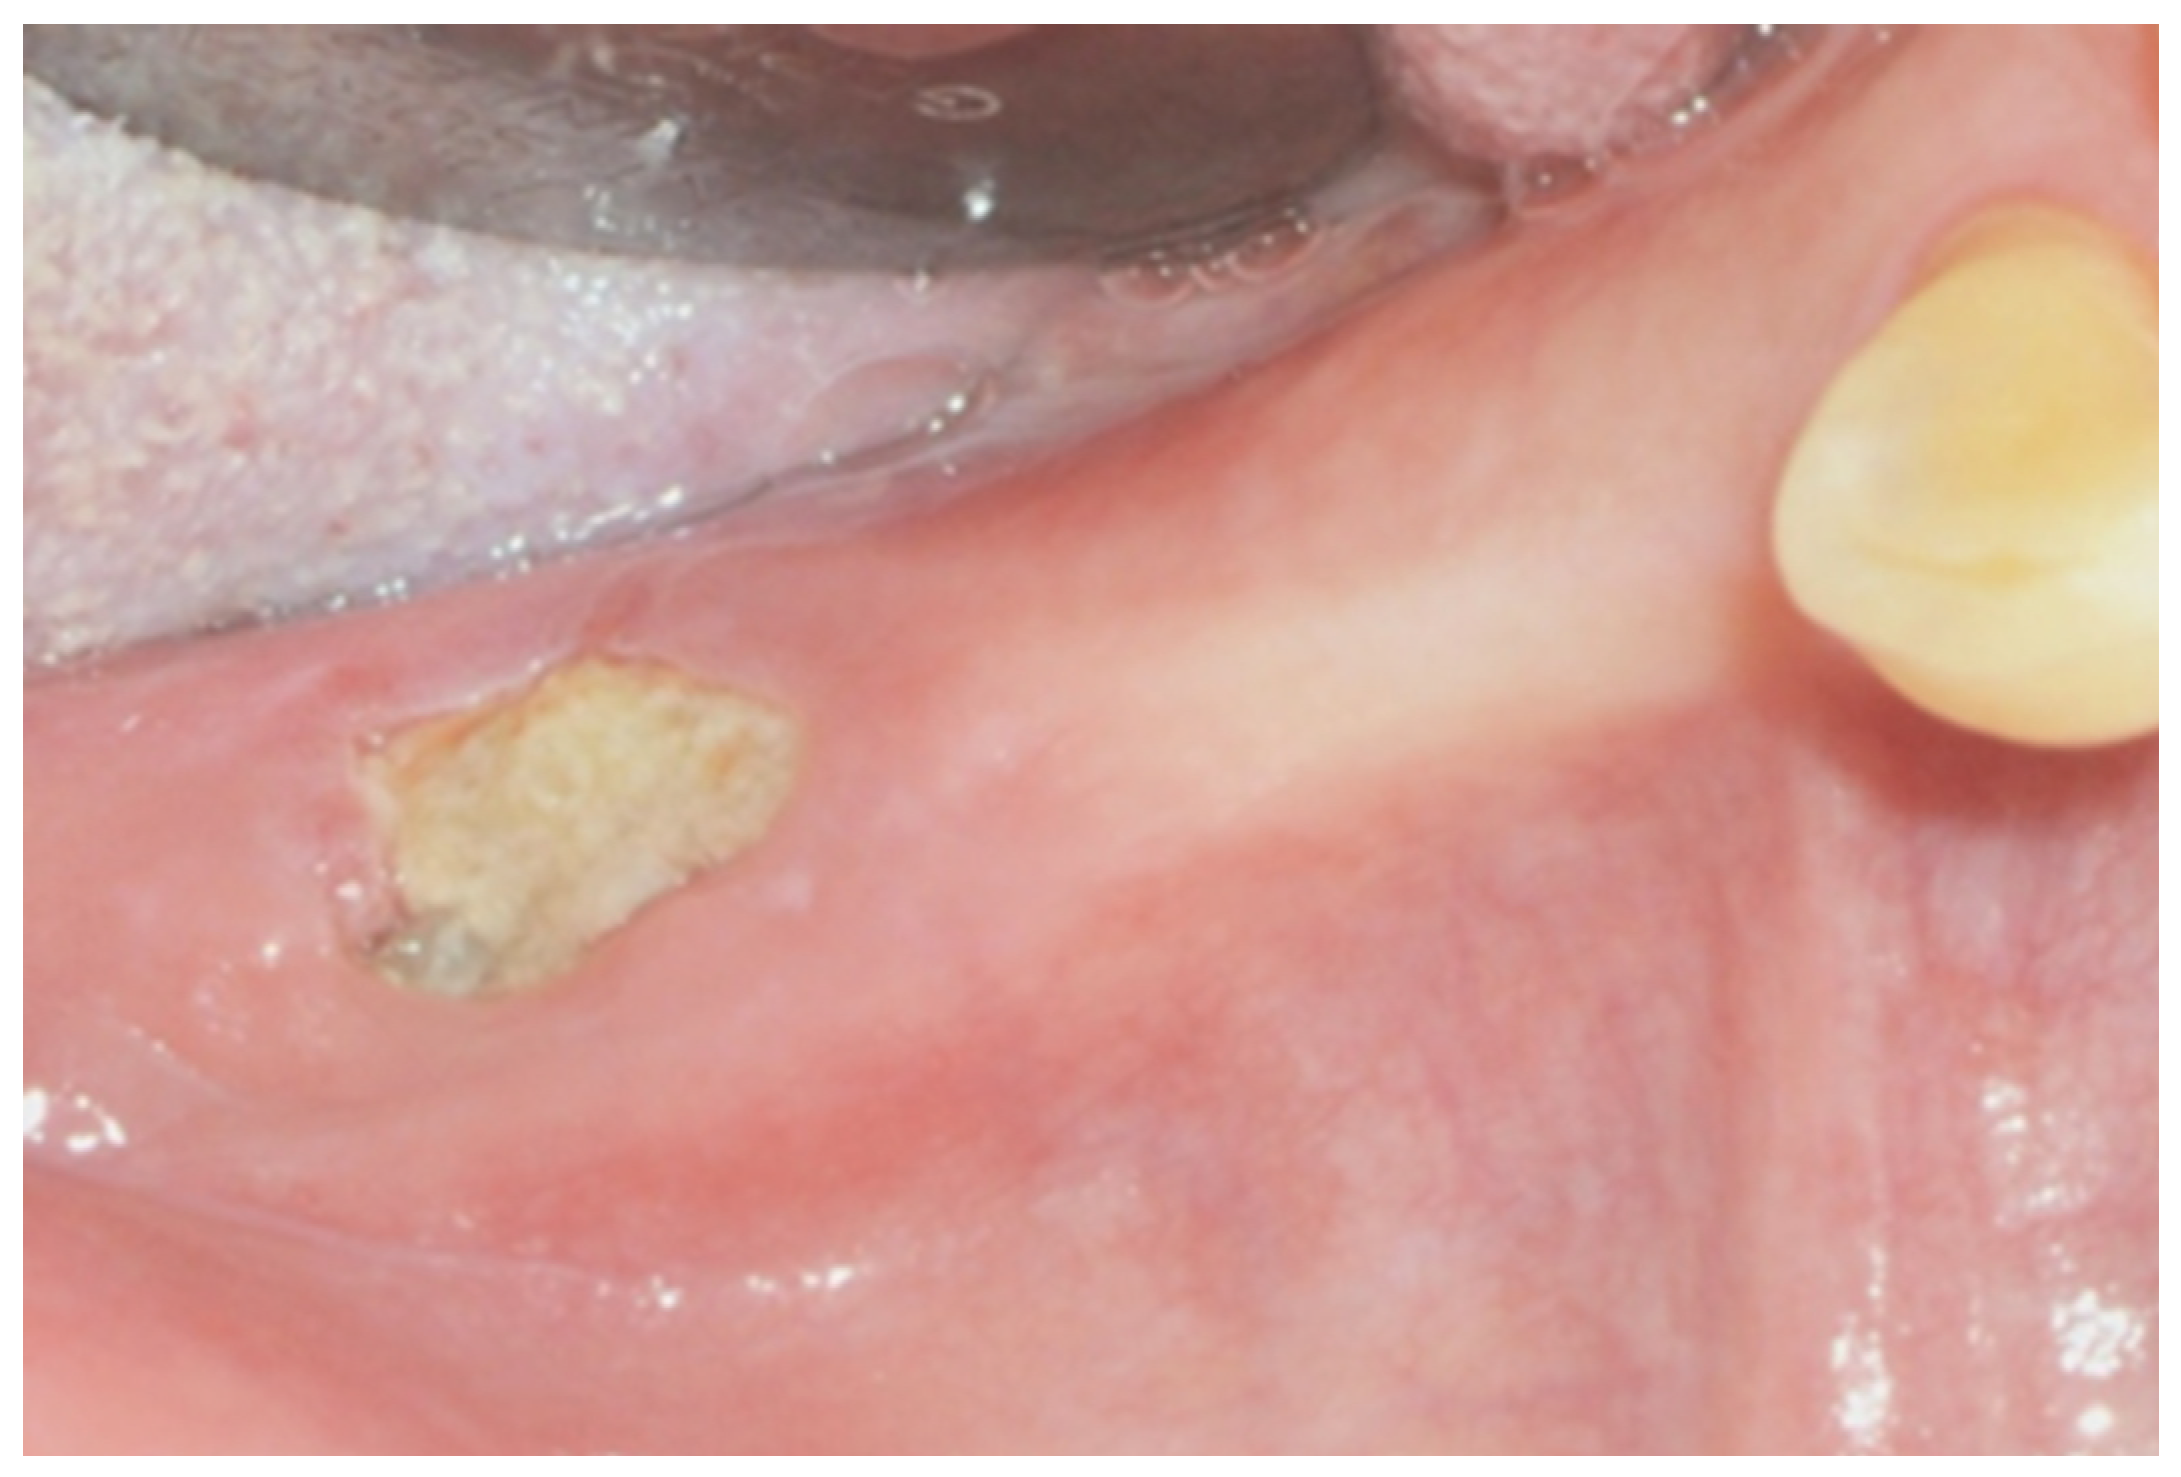

- Complete healing of the wound, without any more bone exposure (if maintained for at least 12 months);

- Incomplete healing with or without stage reduction.